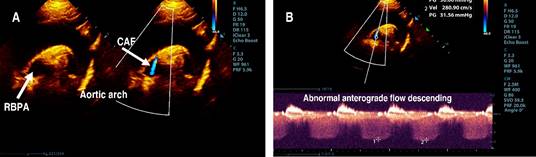

The parasternal short-axis view of the aortic root showed the right coronary artery (RCA) and left coronary artery (LCA) in their appropriate anatomical positions, with the proximal segment of the RCA exhibiting a Z score of 0.2 (Figure 1). However, the suprasternal longitudinal view identified an abnormal vascular structure with anterograde flow descending into the right branch of the pulmonary artery (RBPA) (Figure 2). The suprasternal short-axis view illustrated an anastomosis at the proximal segment of the RBPA, characterized by continuous, pulsatile flow, a maximum recorded velocity of 2.8 m/s, and a maximum gradient of 31 mmHg (Figure 3).

Figure 2: A) Suprasternal long-axis 2D, the transducer tilted anterior (aortic arch to the left and continuous color Doppler): view of abnormal anterograde flow descending in the RBPA (arrow). B) Suprasternal long-axis 2D (aortic arch to the left with continuous Doppler): view of abnormal continuous anterograde flow descending into the RBPA with Vmax: 2.8 m/s.